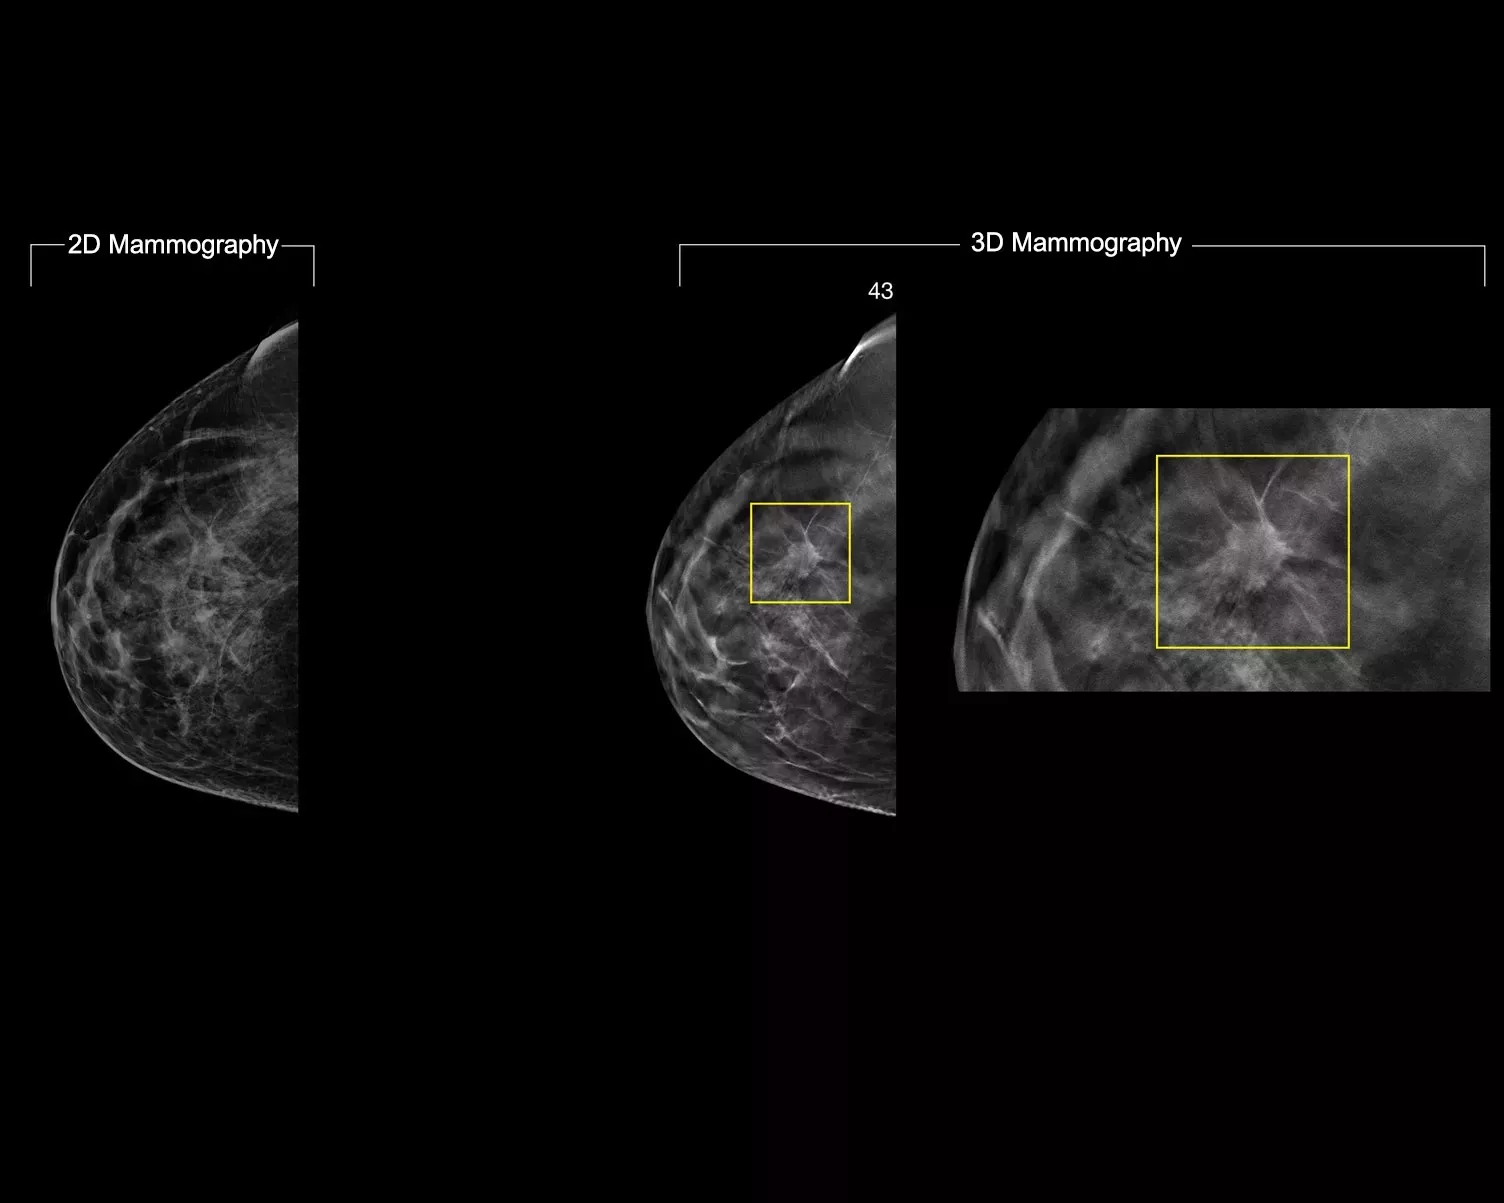

3D マンモグラフィ検査は 2D 単独と比べて優れた臨床パフォーマンスを発揮しますが1-4、より高い画質、より詳細な情報、読影時間の改善、低線量など、さらに多くのことを求める放射線科医もいます。

AI を活用した Intelligent 2D イメージングテクノロジーにより、3D マンモグラフィデータとよく相関する、強固でありながら自然に見える合成 2D 画像が得られます。これにより、放射線科医はマンモグラフィの微妙な特徴や病変の形態を迅速かつ確実に確認できるようになります。*

高解像度の 3D マンモグラフィデータでは、関心対象の特徴がより多く保持されます。AI を活用した分析を使用して、合成 2D 画像中の微妙な組織の特徴や病変が確実に視覚化されます。